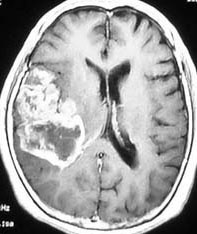

左がガドリニウム増強像で,手術ではこの部分が取れれば全摘出といわれるのですが,実際は右側のフレア画像で白っぽく見える所には腫瘍が滲み込んでいます。この部分を全て摘出してはじめて,画像上の全摘出といいます。全摘出は無理でしょう